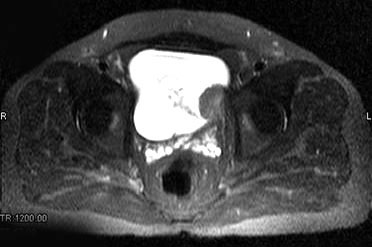

[单选题]男,59岁,血尿1个月,MRI检查如图所示。最可能的诊断是A.膀胱内血块B.膀胱癌C.膀胱结石D.膀胱息肉E.输尿管囊肿